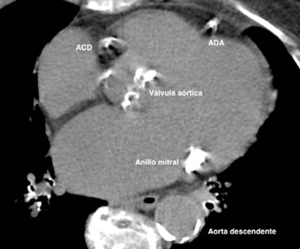

Errores potenciales en el cálculo pueden sobreestimar o subestimar el valor. Por ejemplo, un score erróneamente elevado puede ser debido a la inclusión de estructuras calcificadas en el cálculo, como la pared aórtica, la válvula aórtica y el anillo mitral (figura 1).

Figura 1: En un estudio de score de calcio se puede observar calcificación extracoronaria, por ejemplo, a nivel de la válvula aórtica, anillo mitral y aorta descendente. Se ha demostrado asociación entre la presencia de calcio a nivel extracoronario y eventos cardiovasculares 38,39.